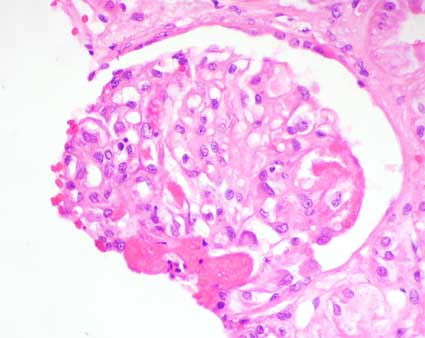

Figura 3.

H&E, X400.